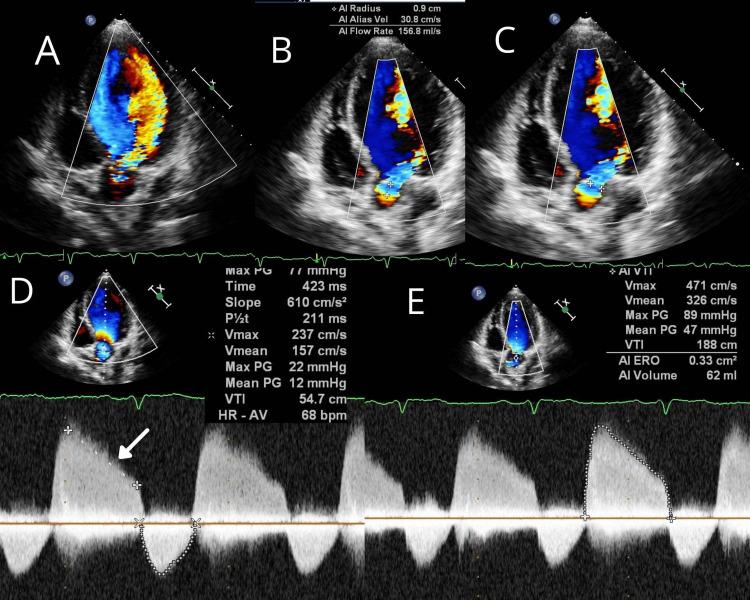

In infective endocarditis, the perivalvular abscess is a known complication with an incidence of more than 22%-29%, but the primary presentation of a healed aortic abscess without any clinical features of infective endocarditis is very rare. These sorts of cases are scarcely documented throughout literature. We present a successful surgical closure of healed perivalvular abscess cavity with aortic valve replacement and mitral valve repair.

在感染性心内膜炎中,瓣周脓肿是一种已知的并发症,发生率超过22% - 29%,但已愈合的主动脉脓肿在没有任何感染性心内膜炎临床特征的情况下首次出现是非常罕见的。这类病例在整个文献中鲜有记载。我们成功地通过主动脉瓣置换和二尖瓣修复对已愈合的瓣周脓肿腔进行了手术闭合。